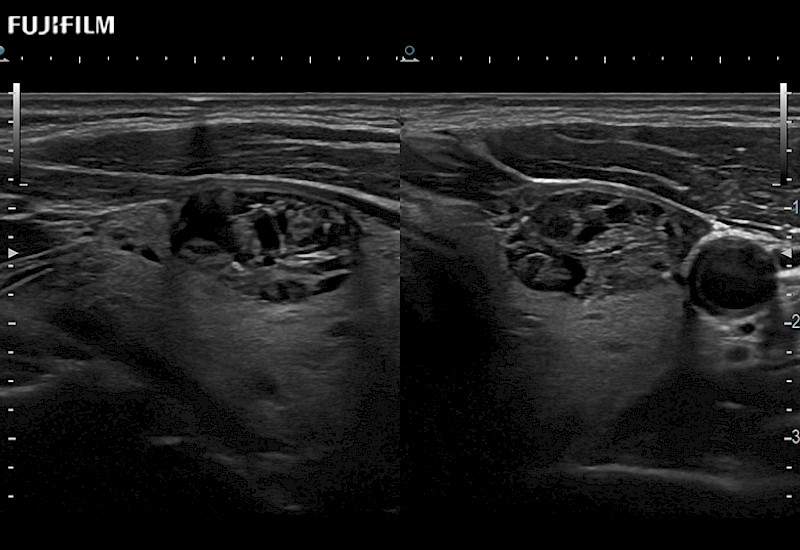

The ARIETTA 750 incorporates all of the proven technologies and functions that medical professionals have come to expect from Fujifilm Healthcare.

ARIETTA 750 is the definitive diagnostic ultrasound solution for any clinical setting - Private Office, Imaging Center, or Hospital. The ARIETTA platform provides the ultimate in clinical performance with its state-of-the-art features and large user-friendly display.

The ARIETTA 650 DI combines trusted Fujifilm Healthcare technologies and features tailored for surgical oncology.

Designed to meet the demands of surgeons, the ARIETTA 650 DI offers precise guidance. Its advanced capabilities and large, intuitive display offer accurate and efficient care in operating rooms and specialized surgical settings.